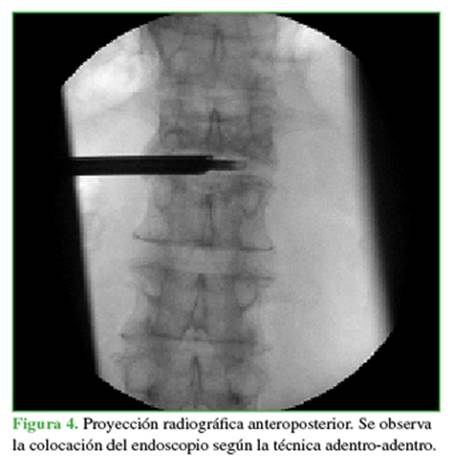

Se utilizó la técnica adentro-adentro (Figura 4) que consiste en trabajar dentro del disco mediante la colocación de la cánula intradiscal. Se procedió a tomar muestras del disco intervertebral de L1-L2 y del platillo vertebral inferior de L1 y del superior de L2 (Figuras 5 y 6). Se enviaron muestras al laboratorio para cultivo y estudio anatomopatológico. Se empleó un sistema de endoscopia de la compañía RIWOspine® que cuenta con un sistema de irrigación-aspiración continua. El procedimiento duró 17 minutos.